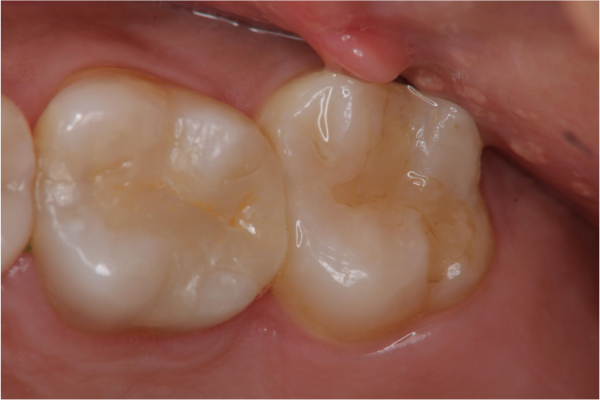

術前、術後比較